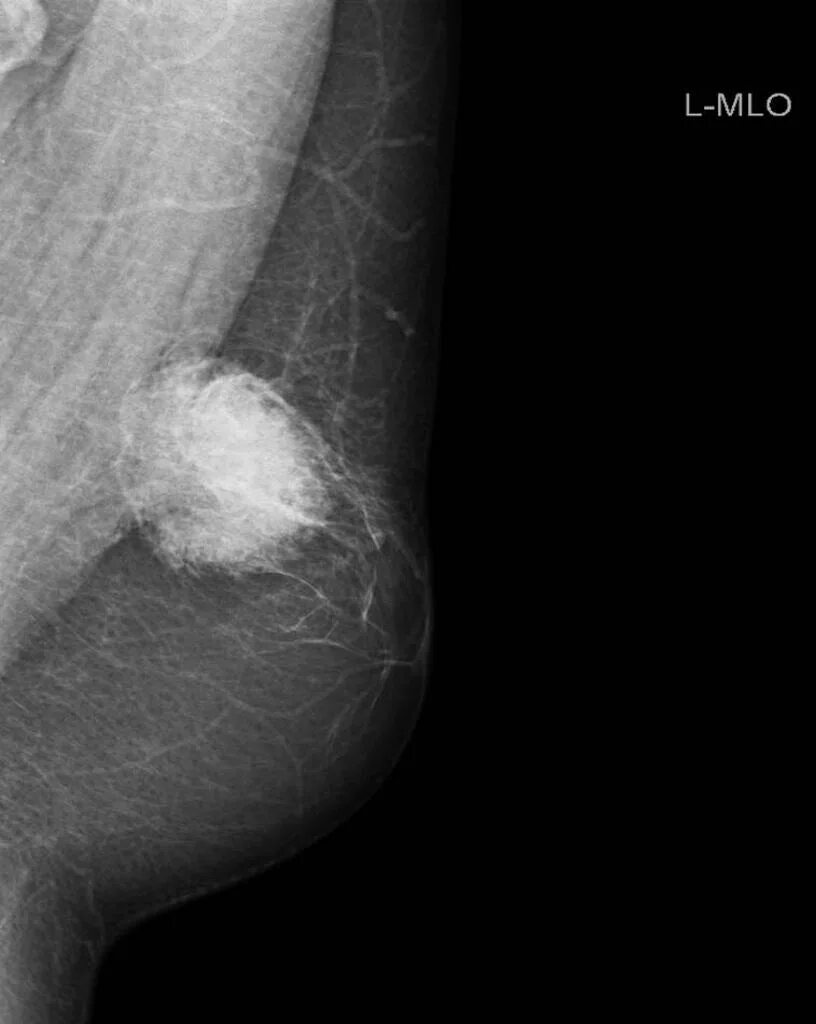

Фиброз грудных